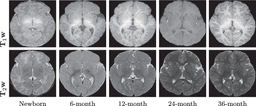

As clinical trials advance, Immunostruct highlights AI’s expanding role in decoding the tumor-immune microenvironment and accelerating translational oncology. Complementary advances in deep learning for biomedical imaging—such as dual-modal frameworks that accurately predict infant brain myelination—demonstrate AI’s broadening impact on diagnostic precision and treatment planning.